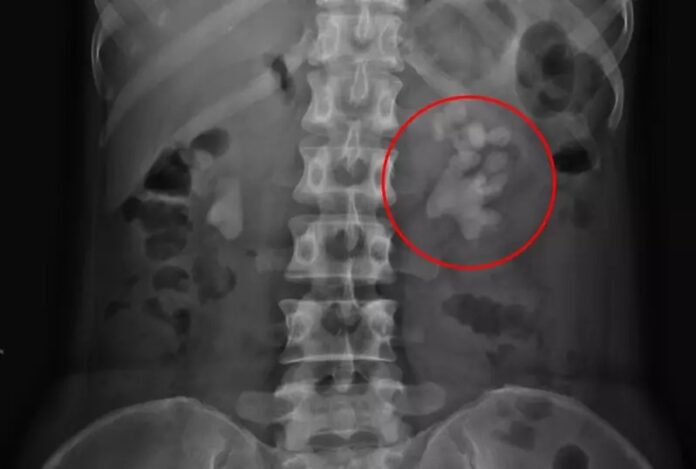

吴俊贤表示,这名女板模师傅三次都是因为小便时感到尿道疼痛而求诊,使用抗生素治疗一个多星期都没有改善,进一步进行X光检查,才发现肾脏长有结石,其中有一次她来就诊时发现两侧肾脏都有结石,左侧肾脏的结石看起来像是巨大的麋鹿角,长度达到了8公分,相当惊人。经过治疗,已完全清除干净。